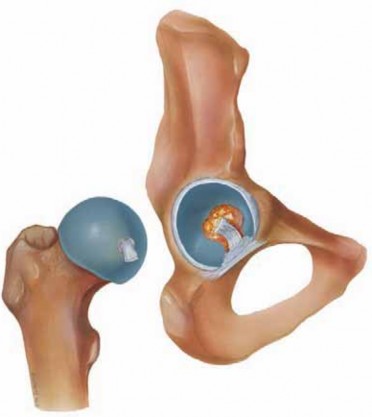

Chapter 25 Arthroscopy for Soft Tissue Pathology of the Hip J. W. Thomas Byrd and MaCalus V. Hogan DEFINITION…

Chapter 27 Snapping Hip J. W. Thomas Byrd and MaCalus V. Hogan DEFINITION Coxa saltans is a term popularized …